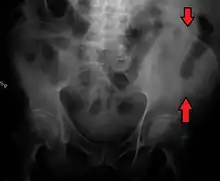

The crest of the ilium (or iliac crest) is the superior border of the wing of ilium and the superiolateral margin of the greater pelvis.

The iliac crest stretches posteriorly from the anterior superior iliac spine (ASIS) to the posterior superior iliac spine (PSIS). Behind the ASIS, it divides into an outer and inner lip separated by the intermediate zone. The outer lip bulges laterally into the iliac tubercle.[1] Palpable in its entire length, the crest is convex superiorly but is sinuously curved, being concave inward in front, concave outward behind.[2]

The top of the iliac crests also marks the level of the fourth lumbar vertebral body (L4), above or below which lumbar puncture may be performed. Furthermore, said level is often referred to as the "intercristal line".